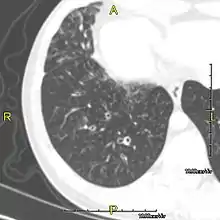

CT image showing dilated and thickened medium-sized airways (bronchiectasis) in a patient with Kartagener syndrome

Oblique sagittal CT image showing lower lobe cylindrical bronchiectasis in the same patient

Around 80% of people with primary ciliary dyskinesia experience respiratory problems beginning within a day of birth. Many have a collapsed lobe of the lung and blood oxygen low enough to require treatment with supplemental oxygen.[1] Within the first few months of life, most develop a chronic mucus-producing cough and runny nose.[1] The main consequence of impaired ciliary function is reduced or absent mucus clearance from the lungs, and susceptibility to chronic recurrent respiratory infections, including sinusitis, bronchitis, pneumonia, and otitis media. Progressive damage to the respiratory system is common, including progressive bronchiectasis beginning in early childhood, and sinus disease (sometimes becoming severe in adults). However, diagnosis is often missed early in life despite the characteristic signs and symptoms.[2] In males, immotility of sperm can lead to infertility, although conception remains possible through the use of in vitro fertilization, there also are reported cases where sperm were able to move.[8] Trials have also shown that there is a marked reduction in fertility in females with Kartagener's syndrome due to dysfunction of the oviductal cilia.[9]